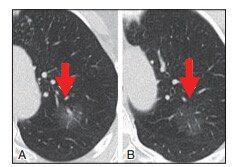

▲图8 A、B为某患者左肺上叶两幅连续的CT轴位图像,图B是随访6个月后。图A显示一非实性结节,包含几个微小泡沫样的实性密度;包括图B在内的其他层面都表现为非实结节。手术后病理证实为AIS。如果连续随访的CT图像显示病灶的实性密度随时间推移不断增加,则说明AISAB是浸润性的早期征兆